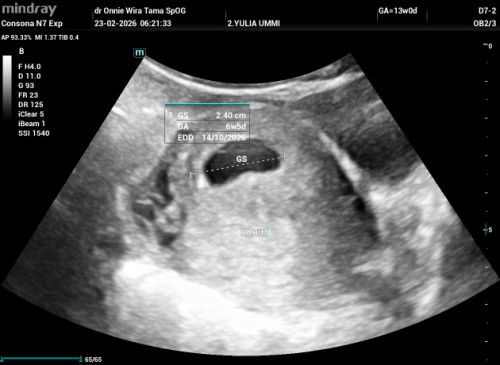

Saya pertama usg didr obgyn di usia 8 minggu menurut hpht tapi setelah diusg ternyata baru 5 Minggu 3 hari setelah itu usg kedua diusia kehamilan 9 minggu dipuskesmas tapi tidak terlihat janinnya dan dinyatakan hamil bo langsung diberi rujukan ke rsud untuk kuret .tapi saya ingin mencari second opinion ke dr obgyn karena tidak keluar flek maupun nyeri perut,setelah usg di dr obgyn terlihat kantung kehamilannya membesar tapi belum terlihat janinnya.setelah itu dokter menyarankan agar 2 minggu lagi datang usg lagi tapi jika masih tidak terlihat di usg 2D baru diusg transvaginal untuk menentukan apakah benar janin tidak berkembang karena saya tidak ada flek sama sekali juga tidak nyeri perut. Apakah ada bunda yang mengalami seperti saya?bisa tolong diceritakan atau beritahu saya harus apa jika memang ada kemungkinan janin masih bisa berkembang.#mohonbantujawabbunda Mohon doanya ya bunda² semoga nanti usg berikutnya ada janinnya dan berkembang dengan baik.